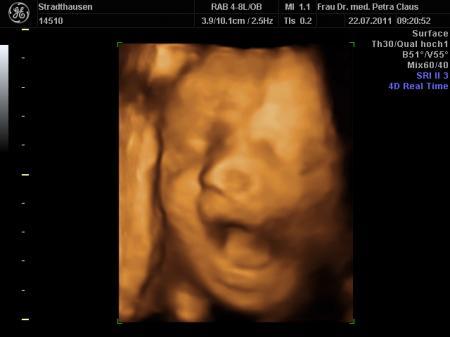

komme grad von der VU und bin ja so ein bisschen megahappy. Endlich hab ich meinen Kleinen wieder im 3D ultralschall gesehen und der war heut vielleicht in Action

...schon beim CTG hat er rumgekaspert, fleißig gegen den Schallkopf getrampelt und sich immer weggedreht, zum Schluss noch nen schönen Schluckauf....voll süß

...alles soweit unauffällig. Dann beim Ultraschall ging es richtig los...Schnute auf, Schnute zu.....wir haben uns köstlich amüsiert. Jedenfalls hat er seinen kleinen Wachstumsrückstand wieder gut aufgeholt, hoffentlich bleibt alles so schön und gesund.

Maße bei 32+4

Gewicht: 2150 gramm

Länge: 42-43 cm....

anbei noch ein paar Bildchen.

Das sind ja echt ganz süsse Bilder

Vor allem die mit dem offenen Mund.